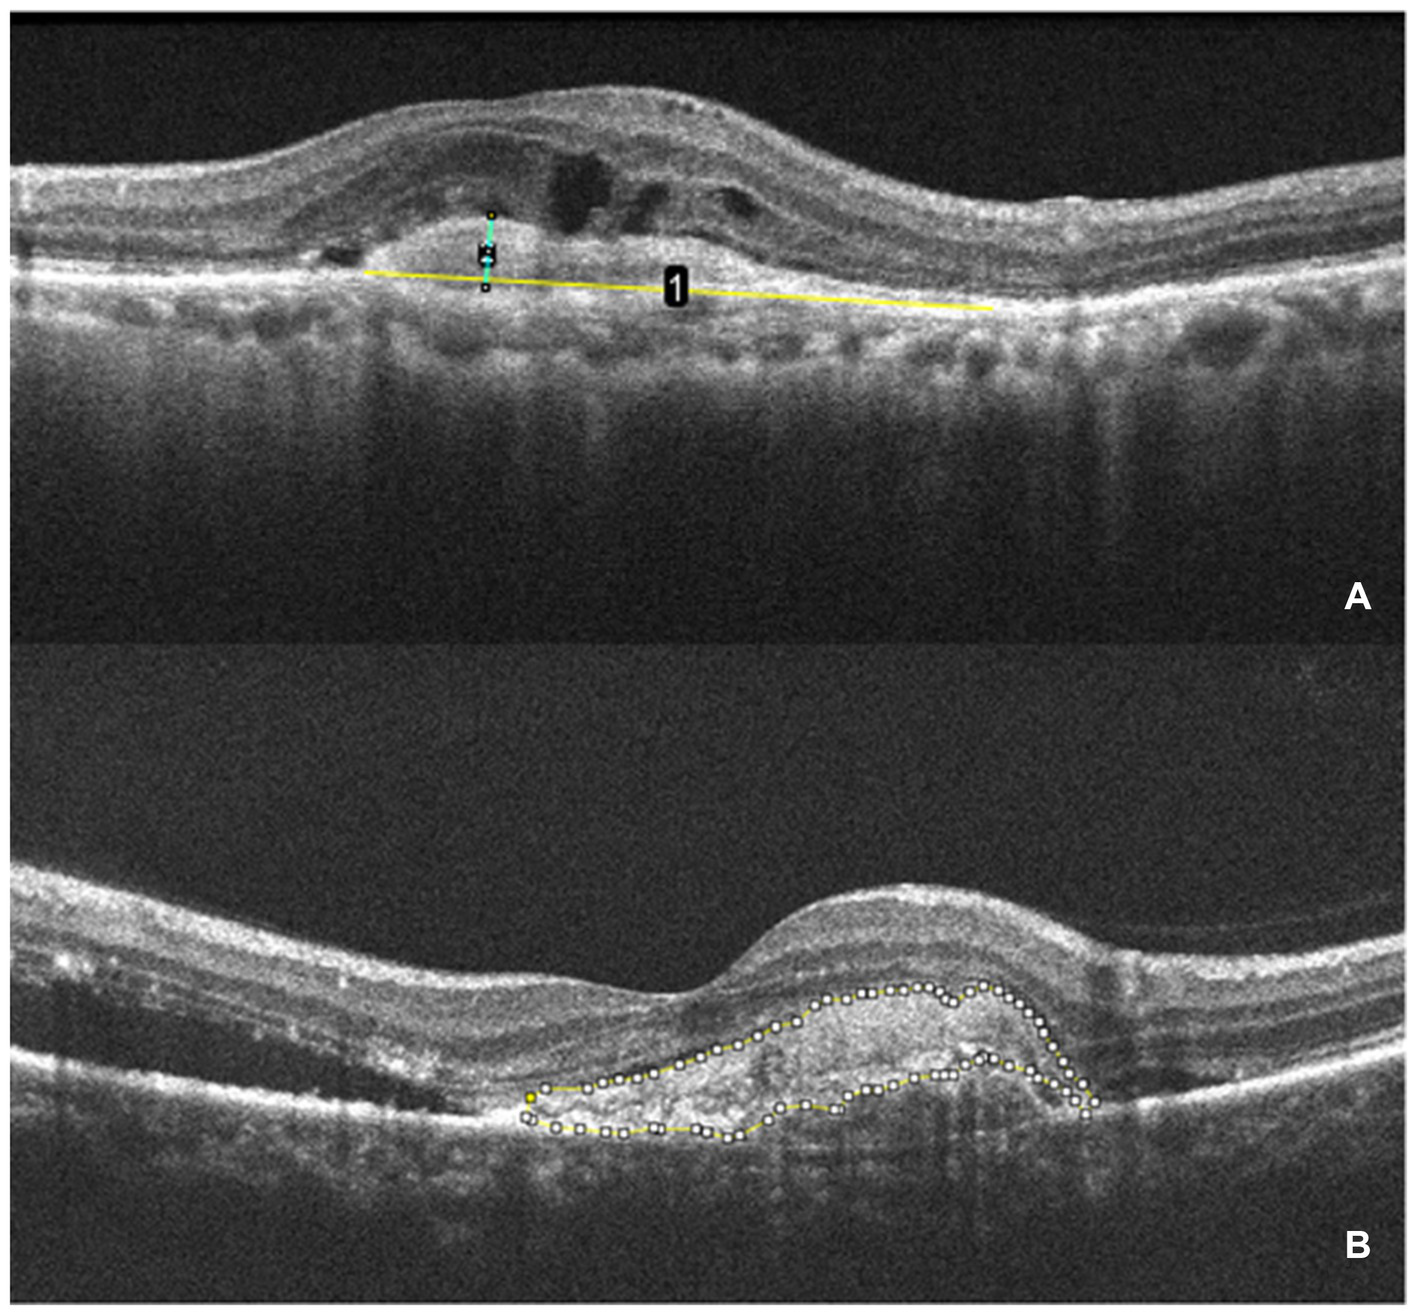

CMT is defined as the vertical distance from the internal limiting membrane of the fovea center to Bruch’s membrane. It was measured using ImageJ (version 1.53 g) software. SHRM is defined on OCT as a highly reflective signal located between the retinal neurosensory layer and the retinal pigment epithelium. It typically consists of macular neovascularization components, blood, lipids, exudates, and fibrin (22, 23). Images capturing horizontal and vertical cross-sections through the foveal center of patients were obtained. The maximum width, thickness, and area of SHRM were measured using ImageJ (version 1.53 g) software. These measurements were taken three times to obtain an average value. The final values were determined by averaging the measurements from both the horizontal and vertical cross-sections. Figure 2 presents an example of SHRM quantification.

Figure 2

The measurement of SHRM. (A) OCT scan showing the maximum width (yellow line 1) and thickness (green line 2) of the SHRM which measured with ImageJ. (B) The area of SHRM was also measured with ImageJ. The yellow line traces the area of SHRM, and the software automatically calculates the area value.